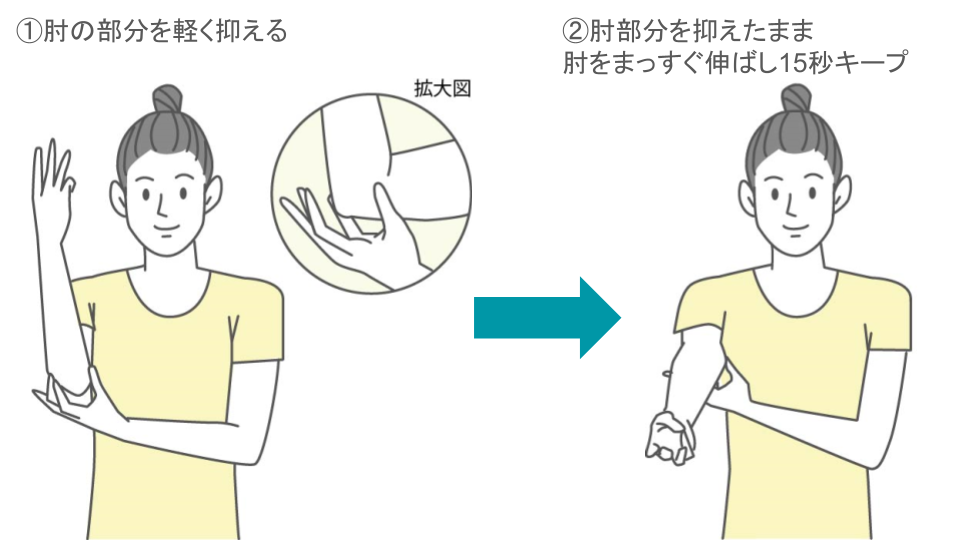

3-2.痛みを緩和させるためのストレッチ

手首や前腕の筋肉を柔らかくするためのストレッチを行うことで、肘の痛みの緩和が見込めます。

これらの筋肉が硬くなると、肘への負担が大きくなり、痛みが出やすくなるからです。

これから紹介するストレッチは、どれも簡単で、場所を選ばずにできます。整形外科での治療と並行して、あるいは、病院で具体的な治療を受けていない場合に、ぜひ試してみてください。

ただし、無理は禁物です!痛みを感じたらすぐに中止し、気持ち良いと感じる範囲で行いましょう。

■肘のストレッチ

いずれのストレッチも難しくはありませんが、以下のようなポイントを押さえておきましょう。

呼吸を止めない(ゆっくりと呼吸しながら行う)

反動をつけない(勢いをつけて行うと、筋肉を傷める可能性がある)

毎日続ける(1日に3〜4回、継続して行う)

痛みがある場合は中止(無理に行うと、症状が悪化する可能性がある)

ストレッチは、肘の痛みを和らげるのに役立ちますが、1回行っただけで劇的に痛みが消えるわけではありませんし、ストレッチだけで痛みが完全に治るわけでもありません。

毎日コツコツと続けることで、少しずつ痛みが和らいでいくことを目指しましょう。